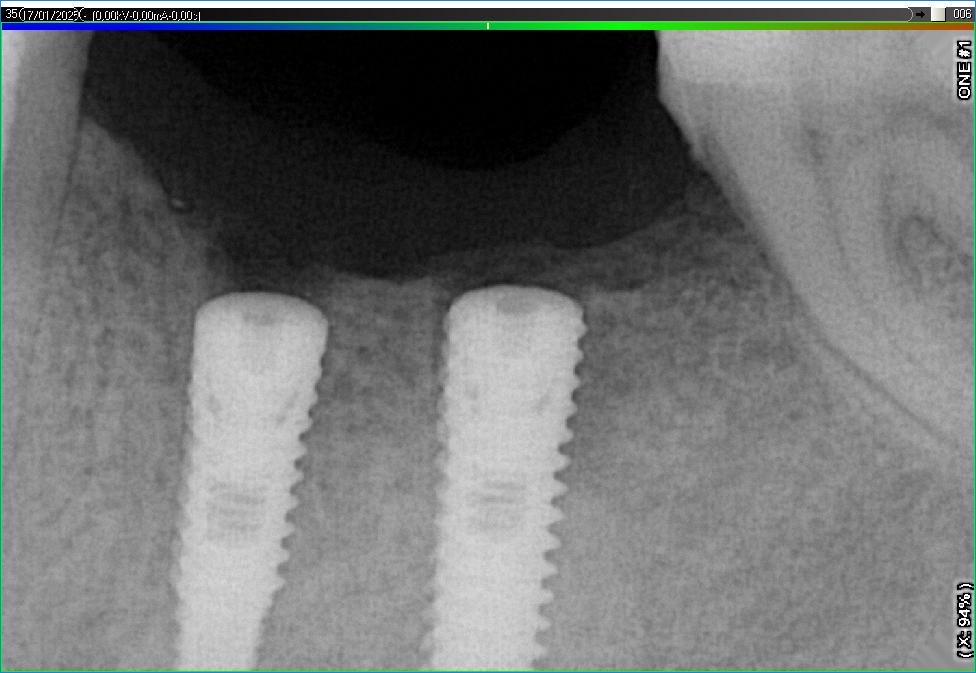

Імплантація